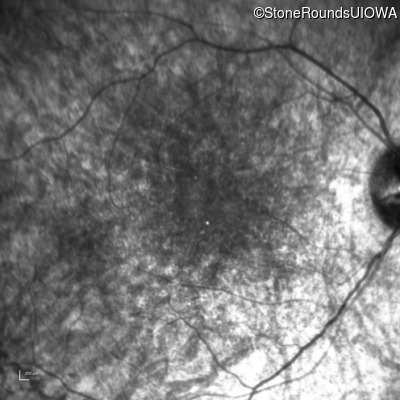

Infrared Fundus Photograph - Left - 10/180 sc

Exemplar